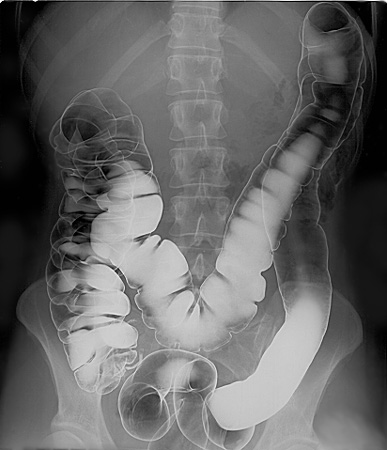

Barium-sulfate contrast materials that are swallowed or administered by mouth (orally) are used to enhance x-ray and CT images of the gastrointestinal (GI) tract, including:

Barium-sulfate contrast materials that are administered by enema (rectally) are used to enhance x-ray and CT images of the lower gastrointestinal (GI) tract (colon and rectum).

Doctors typically request the oral administration of barium-sulfate contrast materials to enhance x-ray and CT images of the gastrointestinal tract, including the pharynx and esophagus, stomach, small intestine or large intestine, also known as the colon. Physicians typically order rectal administration of barium-sulfate contrast to enhance x-ray and CT scans of the small intestine and colon. Clinicians order the intravenous injection of iodine-based contrast to enhance x-ray and CT images of internal organs, such as the heart and lungs, gastrointestinal tract, arteries and veins, the brain, breast tissue and soft tissues of the body, such as muscles and fat.

X-ray examination of the digestive tract can be performed using barium sulfate, a viscous insoluble liquid that absorbs X-rays well.

Therefore, barium sulfate is clearly visible on an X-ray. Liquid barium moves slowly through the digestive tract and is not absorbed in it. All these qualities make barium a good contrast agent for examining the digestive tract.Endoscopy, in which special probes are used to examine internal organs, can sometimes be a more acceptable method than examination with barium. However, barium x-rays are very useful in examining certain functions, such as swallowing, for example.

If an image of the upper digestive tract from the esophagus to the duodenum is to be taken, the patient is given barium sulfate by mouth. Its progress through the digestive tract after barium has passed the duodenum can be traced by taking several pictures at short intervals, or by filming its progress on video.

Barium sulfate is also used for colon imaging. There it is introduced with the help of an enema after preliminary cleansing of the intestines with a laxative. A barium enema is used for examinations to detect abnormalities in the intestine, such as polyps.

The double contrast method is sometimes used. For this, air is introduced into the digestive tract following the barium. Air replaces the contrast agent so that barium remains only on the inner surface of the digestive tract.This method allows you to detect changes characteristic of diseases such as Crohn’s disease.